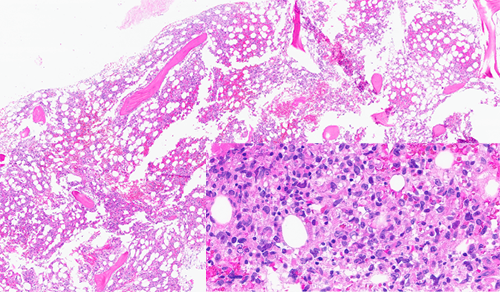

Bone marrow core biopsy showed a packed fibrotic marrow with large atypical lymphoid cells with large pleomorphic nuclei and abundant cytoplasm (shown inset on high-power). Some areas showed a spindled morphology.

However, immunohistochemistry and immunophenotyping by flow cytometry were not consistent with a B-cell lymphoma. The large atypical cells were positive for histiocytic markers such as CD68, CD163, CD4, lysozyme, S100, and IRF8. Cytogenetic studies, including Fluorescent in-situ hybridization (FISH) showed amplification of BCL2 and BCL6 and Next-generation sequencing (NGS) showed mutations of NOTCH2 and SOCS1 with deletions in CDKN2a, ETV6, and CIC. B-cell receptor heavy and light chain gene rearrangement studies by PCR were positive as were studies for T-cell receptor gene rearrangement.